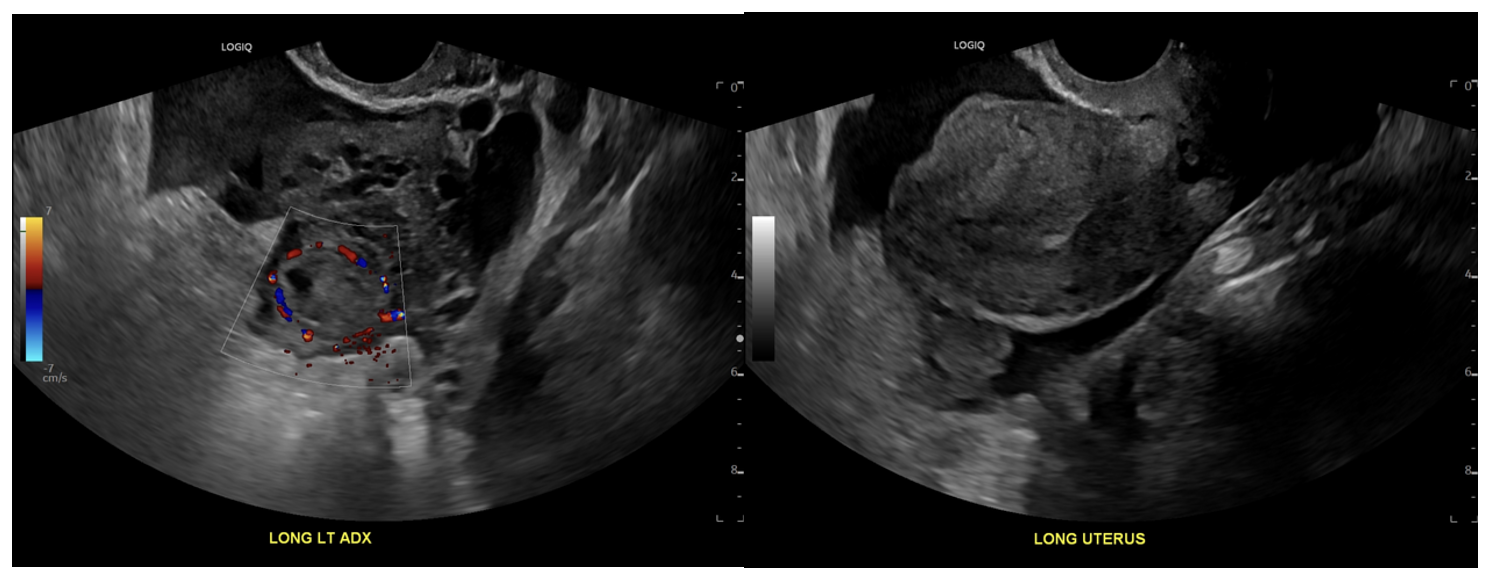

Suggestive signs: heterogenous adnexal mass, “ring of fire” on Doppler, pseudogestational sac, tubal ring sign

Budorick N, Ovarian ectopic pregnancy. Case study, Radiopaedia.org (Accessed on 19 Nov 2025) https://doi.org/10.53347/rID-208112

Knipe H, Tubal ectopic pregnancy. Case study, Radiopaedia.org (Accessed on 19 Nov 2025) https://doi.org/10.53347/rID-36812.